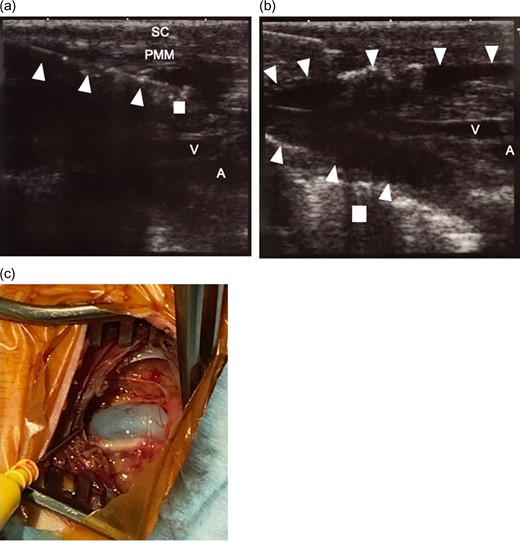

(a) Ultrasound-guided tumescent local analgesia technique. Tumescent local analgesic solution was infused under ultrasound image guidance. The 18-gauge needle can be easily identified (triangle. The tip of the needle is indicated by square.) and solution infusion can be observed. (b) After infusion of the solution. The area under the pectoralis major muscle was dissected and a pocket was made (surrounded by triangle) for placing the pacemaker. The surrounding tissue blood vessels were also dissected. Square indicates the first rib. c. Picture of the operation site after exposure of the axillary vein. Vasoconstriction of the axillary vein did not hinder the placement of the leads using purse string suture and Seldinger technique. The surrounding tissue is edematous because of tumescent local analgesia solution injection. But the we could easily identify the anatomical structures. The bleeding was limited due to the epinephrine in the tumescent local analgesia solution. SC, subcutaneous tissue; PMM, pectoralis major muscle; V, axillary vein; A, axillary artery.

The epinephrine in TLA facilitates vasoconstriction [8]. The vasoconstriction in small vessels was sufficient to achieve hemostasis, however, constriction of the axillary vein did not complicate the introduction of the leads (Fig. 2).